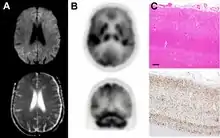

Brain FDG PET-CT tends to be markedly abnormal, and is increasingly used in the investigation of dementias.

- Patients with CJD will normally have hypometabolism on FDG PET.[50]

Testing of tissue remains the most definitive way of confirming the diagnosis of CJD, although it must be recognized that even biopsy is not always conclusive.[51]

In one-third of people with sporadic CJD, deposits of "prion protein (scrapie)", PrPSc, can be found in the skeletal muscle and/or the spleen.[52] Diagnosis of vCJD can be supported by biopsy of the tonsils, which harbor significant amounts of PrPSc; however, biopsy of brain tissue is the definitive diagnostic test for all other forms of prion disease. Due to its invasiveness, biopsy will not be done if clinical suspicion is sufficiently high or low. A negative biopsy does not rule out CJD, since it may predominate in a specific part of the brain.[53]

The classic histologic appearance is spongiform change in the gray matter: the presence of many round vacuoles from one to 50 micrometers in the neuropil, in all six cortical layers in the cerebral cortex or with diffuse involvement of the cerebellar molecular layer.[54] These vacuoles appear glassy or eosinophilic and may coalesce. Neuronal loss and gliosis are also seen.[55] Plaques of amyloid-like material can be seen in the neocortex in some cases of CJD.[56]

However, extra-neuronal vacuolization can also be seen in other disease states. Diffuse cortical vacuolization occurs in Alzheimer's disease, and superficial cortical vacuolization occurs in ischemia and frontotemporal dementia. These vacuoles appear clear and punched-out. Larger vacuoles encircling neurons, vessels, and glia are a possible processing artifact.[53]